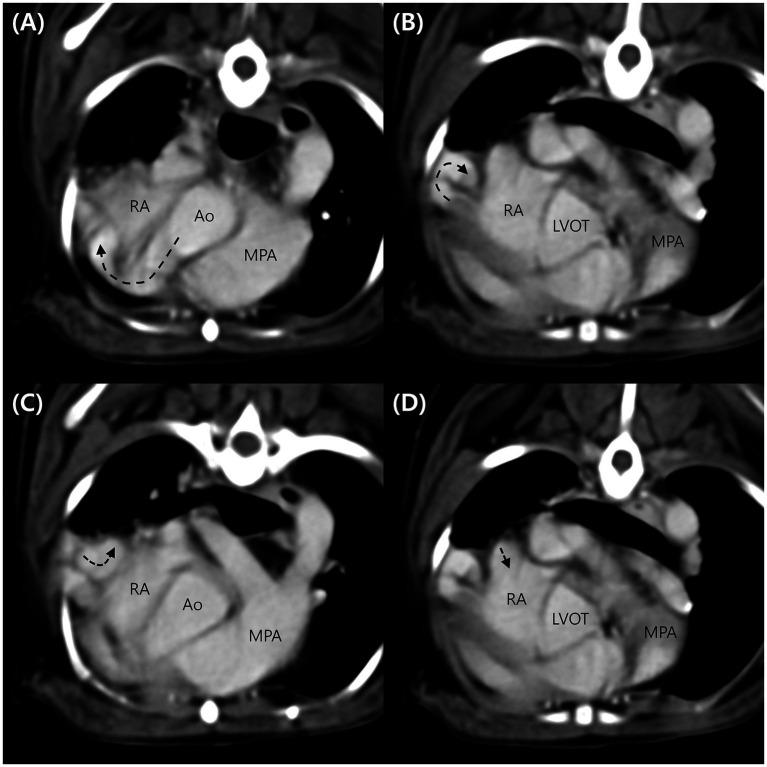

A 7-year-old castrated male Pomeranian dog weighing 5 kg presented with a right-sided continuous murmur without any clinical signs. Thoracic radiographs indicated cardiomegaly and right atrial (RA) bulging. Echocardiography revealed a tunnel originating from the right coronary sinus of Valsalva and terminating in the RA. Contrast echocardiography revealed pulmonary arteriovenous anastomoses. Computed tomography (CT) demonstrated a tortuous shunting vessel that originated from the aorta extending in a ventral direction, ran along the right ventricular wall, and was inserted into the RA. Based on these diagnostic findings, the dog was diagnosed with the aorta-RA tunnel. At the 1-year follow-up visit without treatment, the dog showed no significant change except for mild left ventricular volume overload and mildly decreased contractility. To the best of our knowledge, this is the first case report of an aorta-RA tunnel that has been described in detail using echocardiography and CT in a dog. In conclusion, the aorta-RA tunnel should be included in the clinical differential diagnoses if a right-sided continuous murmur is heard or shunt flow originating from the aortic root is identified.

一只7岁、体重5千克的去势雄性博美犬出现右侧连续性杂音,但无任何临床症状。胸部X线片显示心脏肥大和右心房(RA)膨出。超声心动图显示一条起源于主动脉窦右冠状动脉且终止于右心房的通道。对比超声心动图显示肺动静脉吻合。计算机断层扫描(CT)显示一条迂曲的分流血管,起源于主动脉,向腹侧延伸,沿右心室壁走行,并插入右心房。基于这些诊断结果,该犬被诊断为主动脉 - 右心房通道。在未经治疗的1年随访中,除轻度左心室容量超负荷和轻度收缩力下降外,该犬无明显变化。据我们所知,这是首例使用超声心动图和CT对犬主动脉 - 右心房通道进行详细描述的病例报告。总之,如果听到右侧连续性杂音或发现源自主动脉根部的分流血流,临床鉴别诊断应包括主动脉 - 右心房通道。